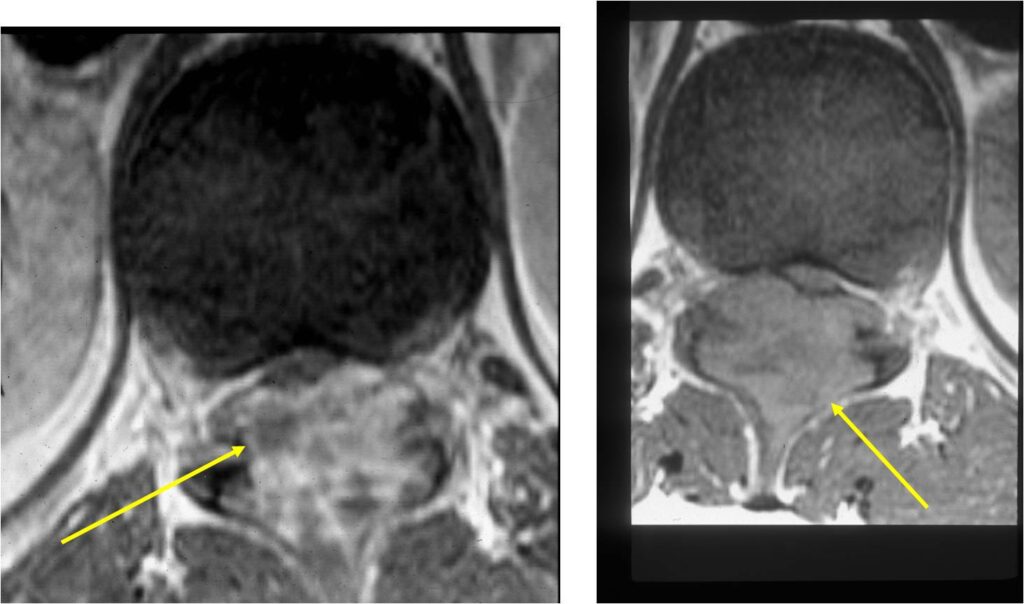

MRI:

- Also useful in determining extent

- There is often extensive edema around the tumor in the surrounding bone and soft tissues that can lead to a misdiagnosis of a malignant tumor.

- Spine (40% of cases; usually posterior elements)

- Spinal lesions may be accompanied by muscle spasms, scoliosis and neurological manifestations